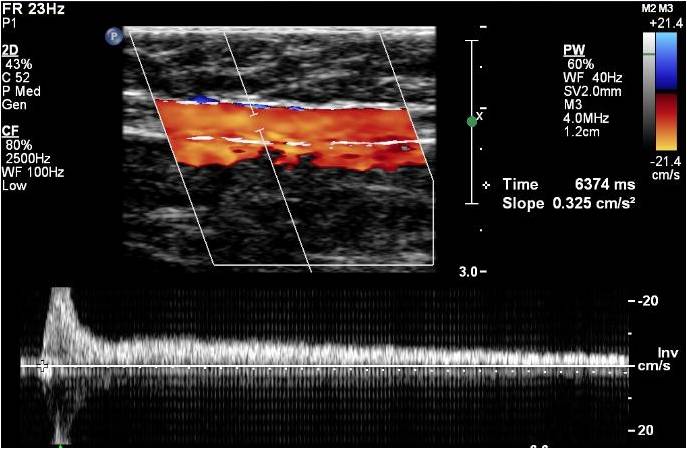

How To Case Study: Deep Vein Thrombosis Detection With ...

Visit http://www.sonosite.com/education for more videos like this. Learn about how to detect deep vein thrombosis using portable ultrasound from Dr Perera in this first part of a 2 part series. Visit http://www.sonosite.com/education for more videos like this. ... View Video

Venous US Of Lower-Extremity Deep Venous Thrombosis: When Is ...

Venous US of Lower-Extremity Deep Venous Thrombosis: When Is US Insufficient?1 Damian E. Dupuy, MD low-up of prior DVT. In this setting, US images of a lower-extremity vein can be equivocal. At this point, one could elect to repeat US in 3 days racy of color Doppler ultrasound in the ... Retrieve Doc

Venous Duplex Ultrasound Of The Lower Extremity In The ...

Venous Duplex Ultrasound of the Lower Extremity in the Diagnosis of Deep Venous Thrombosis 23 Bruce L. Mintz and Robert W. Hobson 11 Introduction Venous Duplex Ultrasound in the Diagnosis of DVT 325 Ag.23.3. ... Read Here